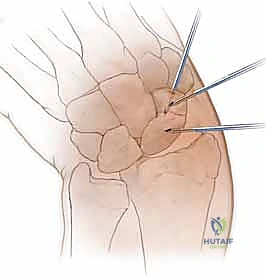

الخطوة 2: تحديد مسار المسمار بدقة (Guidewire Placement)

هذه هي الخطوة الأكثر أهمية والتي تتطلب مهارة استثنائية. يقوم د. هطيف بعمل شق صغير جداً (بضعة مليمترات). باستخدام جهاز الأشعة، يقوم بإدخال سلك معدني